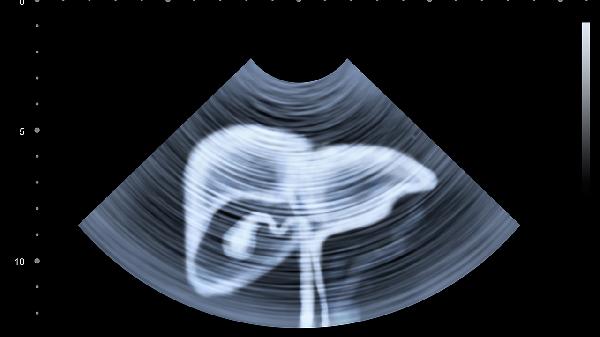

超声显像在骨科围术期有什么应用

超声显像在骨科围术期主要应用于术前评估、术中导航、术后监测、疼痛管理和康复指导五个方面。

实时超声引导能辅助完成闭合复位内固定术,避免多次X线暴露。在脊柱手术中可观察硬膜囊位置,降低神经损伤概率。关节置换术中可动态监测假体安放角度。

超声能早期发现血肿、感染等并发症,通过观察肌骨界面渗出液变化判断炎症程度。多普勒模式可评估吻合血管通畅性,对皮瓣存活监测具有独特优势。

超声引导下神经阻滞能精确定位目标神经,提高镇痛效果并减少麻醉药用量。可视化注射可避免血管穿刺风险,特别适用于肥胖患者解剖标志不清的情况。